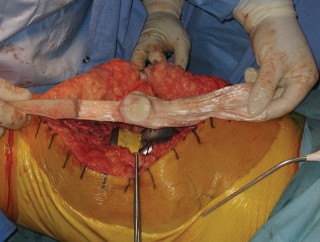

Tibial Host Bed Preparation and Fixation

A corresponding trough is created in the host anterior tibia, slightly medial to the native tibial tubercle to optimize the Q-angle. The trough is undersized by 1 to 2 millimeters to ensure a rigid press-fit of the allograft bone block.

The allograft bone block is impacted into the host trough. Fixation is achieved using the previously placed cerclage wires or cables, which are passed around the proximal tibia or through transverse drill holes in the tibial metaphysis. Supplemental fixation with anterior-to-posterior cortical screws can be utilized to enhance rotational stability and resist the massive pull-out forces generated during knee flexion.